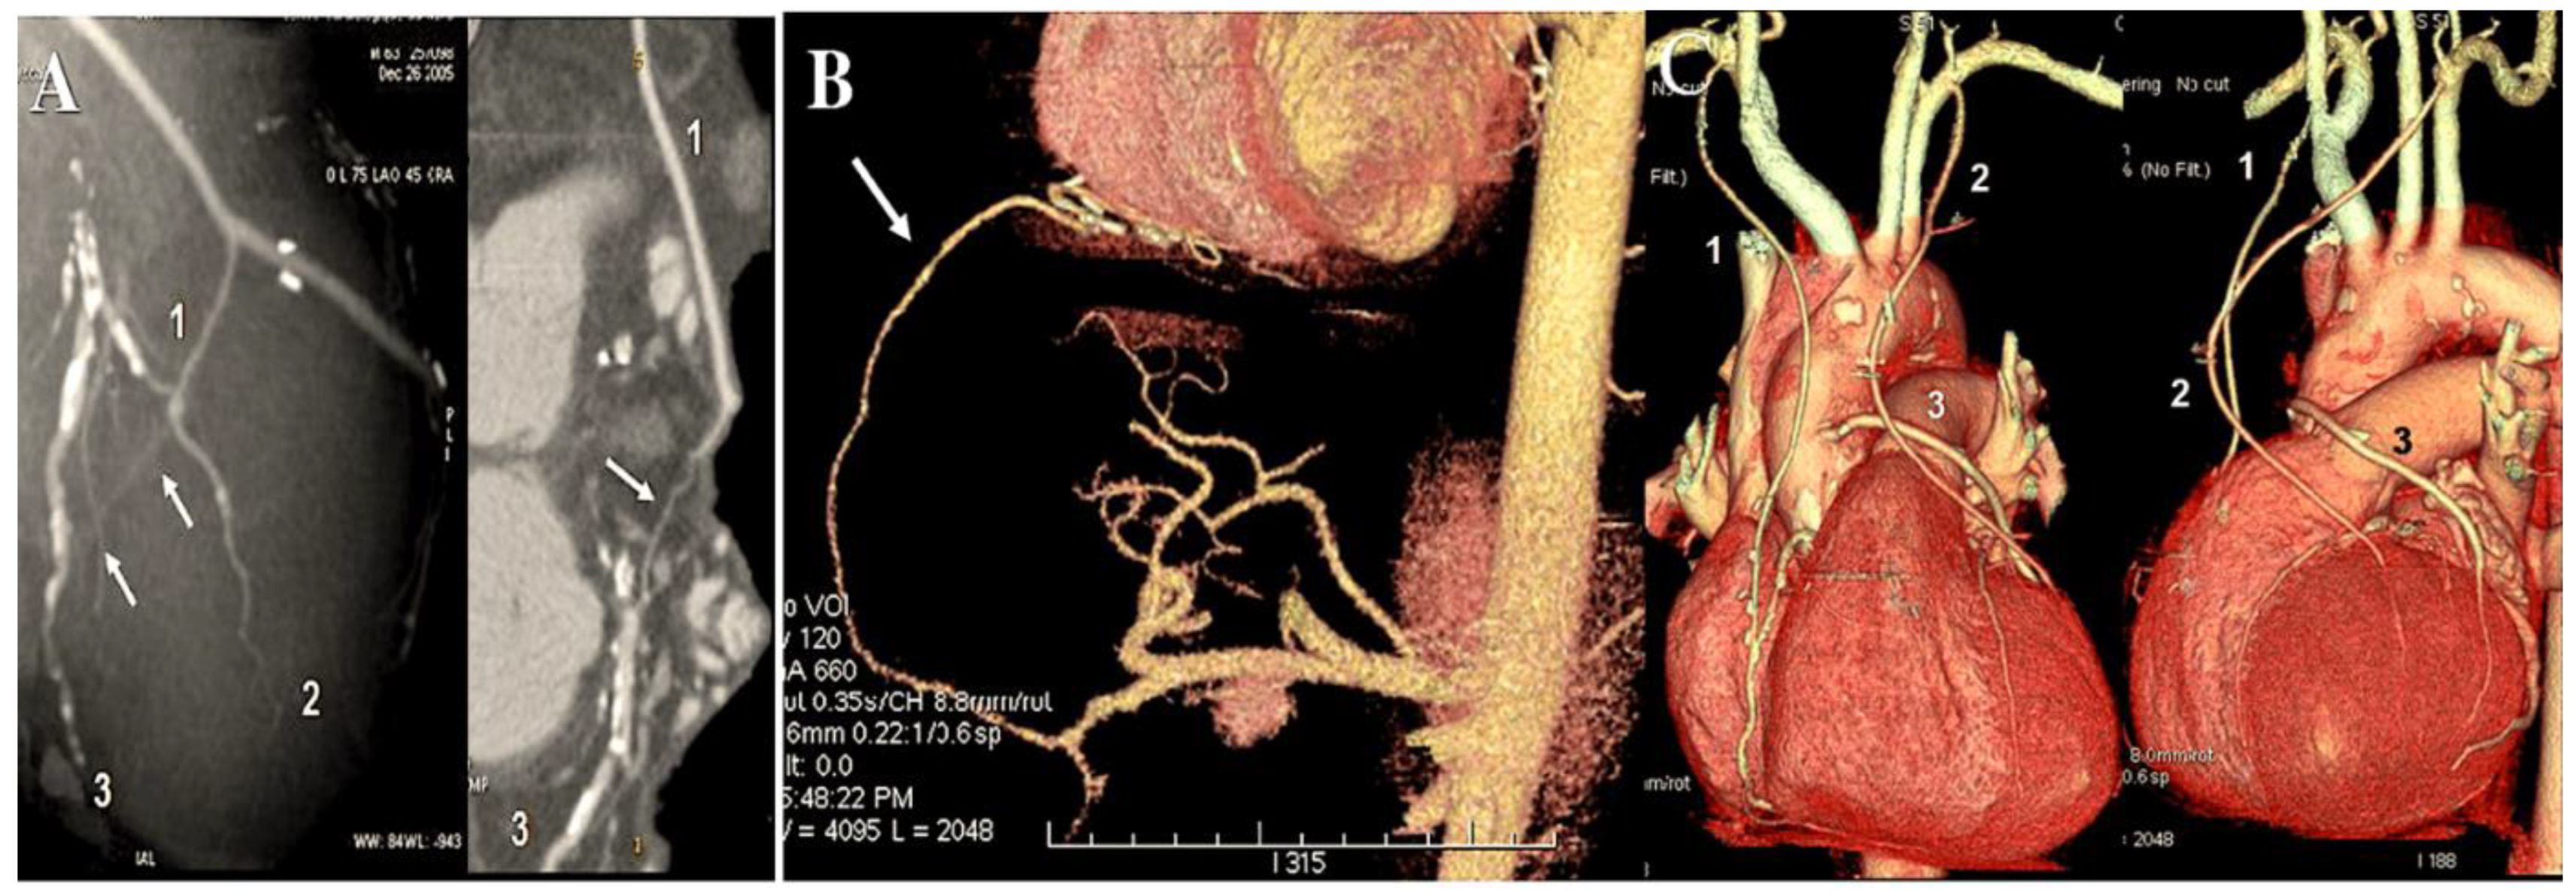

- Miwa S, Desai N, Koyama T, Chan E, Cohen EA, Fremes SE; Radial Artery Patency Study Investigators. Radial artery angiographic string sign: clinical consequences and the role of pharmacologic therapy. Ann Thorac Surg 2006. 81:112-8. [CrossRef]

- Merlo M, Terzi A, Tespili M, Ferrazzi P. Reversal of radial artery « string sign » at 6 months follow-up. Eur J Cardiothorac Surg 2003. 23:432-4 . [CrossRef]

- Manabe S, Fukui T, Shimokawa T, Tabata M, Katayama Y, Morita S, Takanashi S. Increased graft occlusion or string sign in composite arterial grafting for mildly stenosed target vessels. Ann Thorac Surg 2010. 89:683-7. [CrossRef]

- Maniar HS, Sundt TM, Barner HB, Prasad SM, Peterson L, Absi T, Moustakidis P. Effect of target stenosis and location on radial artery graft patency. J Thorac Cardiovasc Surg 2002. 123:45–52. [CrossRef]

- Gaudino M, Alessandrini F, Pragiola C, Cellini C, Glieac F, Luciani N, Giroal F, Possati G. Effect of target artery location and severity of stenosis on long term patency of aorta-anastomosed vs internal thoracic artery anastomosed radial artery grafts. Eur J Cardiothorac Surg 2004. 25:424–428. [CrossRef]

- Yie K, Na CY, Oh SS, Kim JH, Shinn SH, Seo HJ. Angiographic results of the radial artery graft patency according to the degree of native coronary stenosis. Eur J Cardiothorac Surg. 2008 Mar;33(3):341-8. [CrossRef]